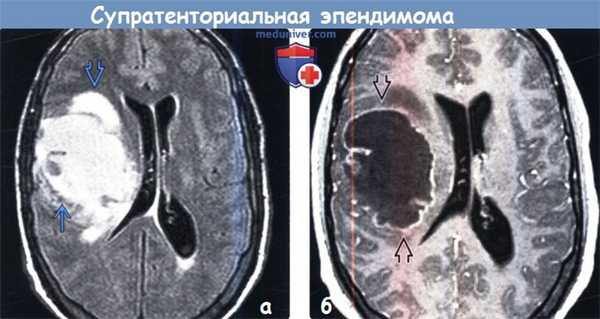

(а) MPT, FLAIR, аксиальный срез: в правом полушарии определяется крупное кистозное объемное образование с перифокальным отеком и компрессией правого бокового желудочка с минимальным смещением срединных структур.

(б) МРТ, постконтрастное Т1-ВИ, аксиальный срез: у того же пациента определяется периферийный характер накопления контраста вокруг неконтрастируемого кистозного компонента. При хирургической операции была диагностирована супратенториальная эпендимома (СТЭ). Данная супратенториальная эпендимома (СТЭ) не имеет связи с желудочковой системой.